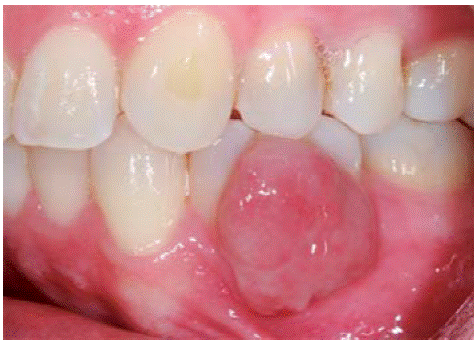

Al examen clínico se observa lesión gingival inflamatoria a nivel de piezas 3.4 y 3.5, de aproximadamente 15x9 mm, cubriendo la cara vestibular de la corona clínica, de consistencia firme, lobulada, textura rugosa y sangrante ante el estímulo (Figuras 1 y 2). A la evaluación periodontal no se detectaron bolsas periodontales, se observó presencia de placa, obteniéndose un índice de higiene oral (O'Leary) de 18.75%.

Al examen clínico se observa lesión gingival inflamatoria a nivel de las piezas 1.1 y 2.1, de aproximadamente 9 X 9 mm, cubriendo un tercio de la corona clínica, de consistencia firme, lobulada, textura rugosa, sangrante ante el estímulo y asintomática (Figura 9). A la evaluación periodontal no presentaba bolsas periodontales, sin embargo, se observó presencia de placa, obteniéndose un índice de higiene oral (O'Leary) de 50%.

Al examen clínico se observa una lesión gingival inflamatoria a nivel de las piezas 1.3 y 1.5, de aproximadamente 9x9 mm, cubriendo un tercio de la corona clínica, de consistencia firme, lobulada, textura lisa, sangrante ante el estímulo y asintomática (Figuras 21 y 22).